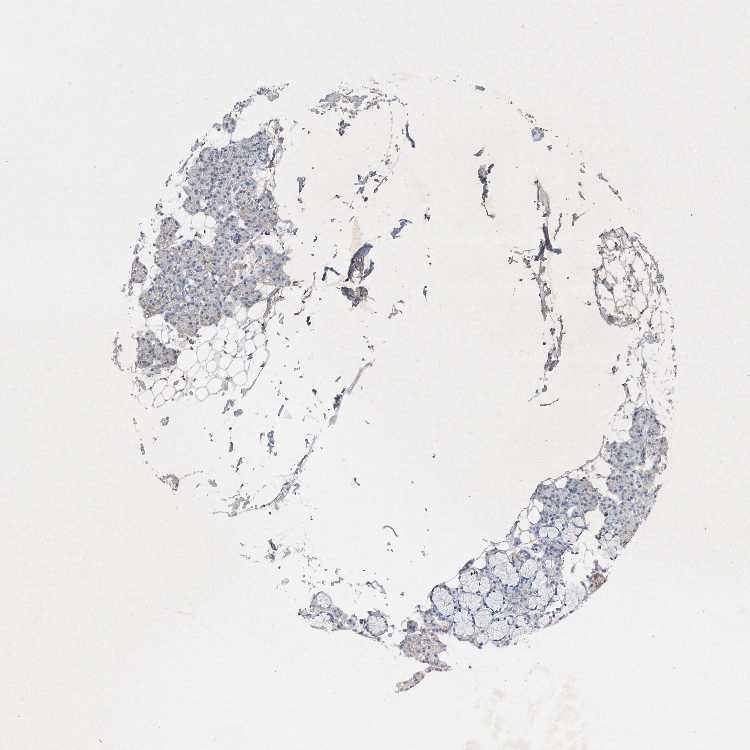

Antibody CAB025945

Glandular cells Not detected